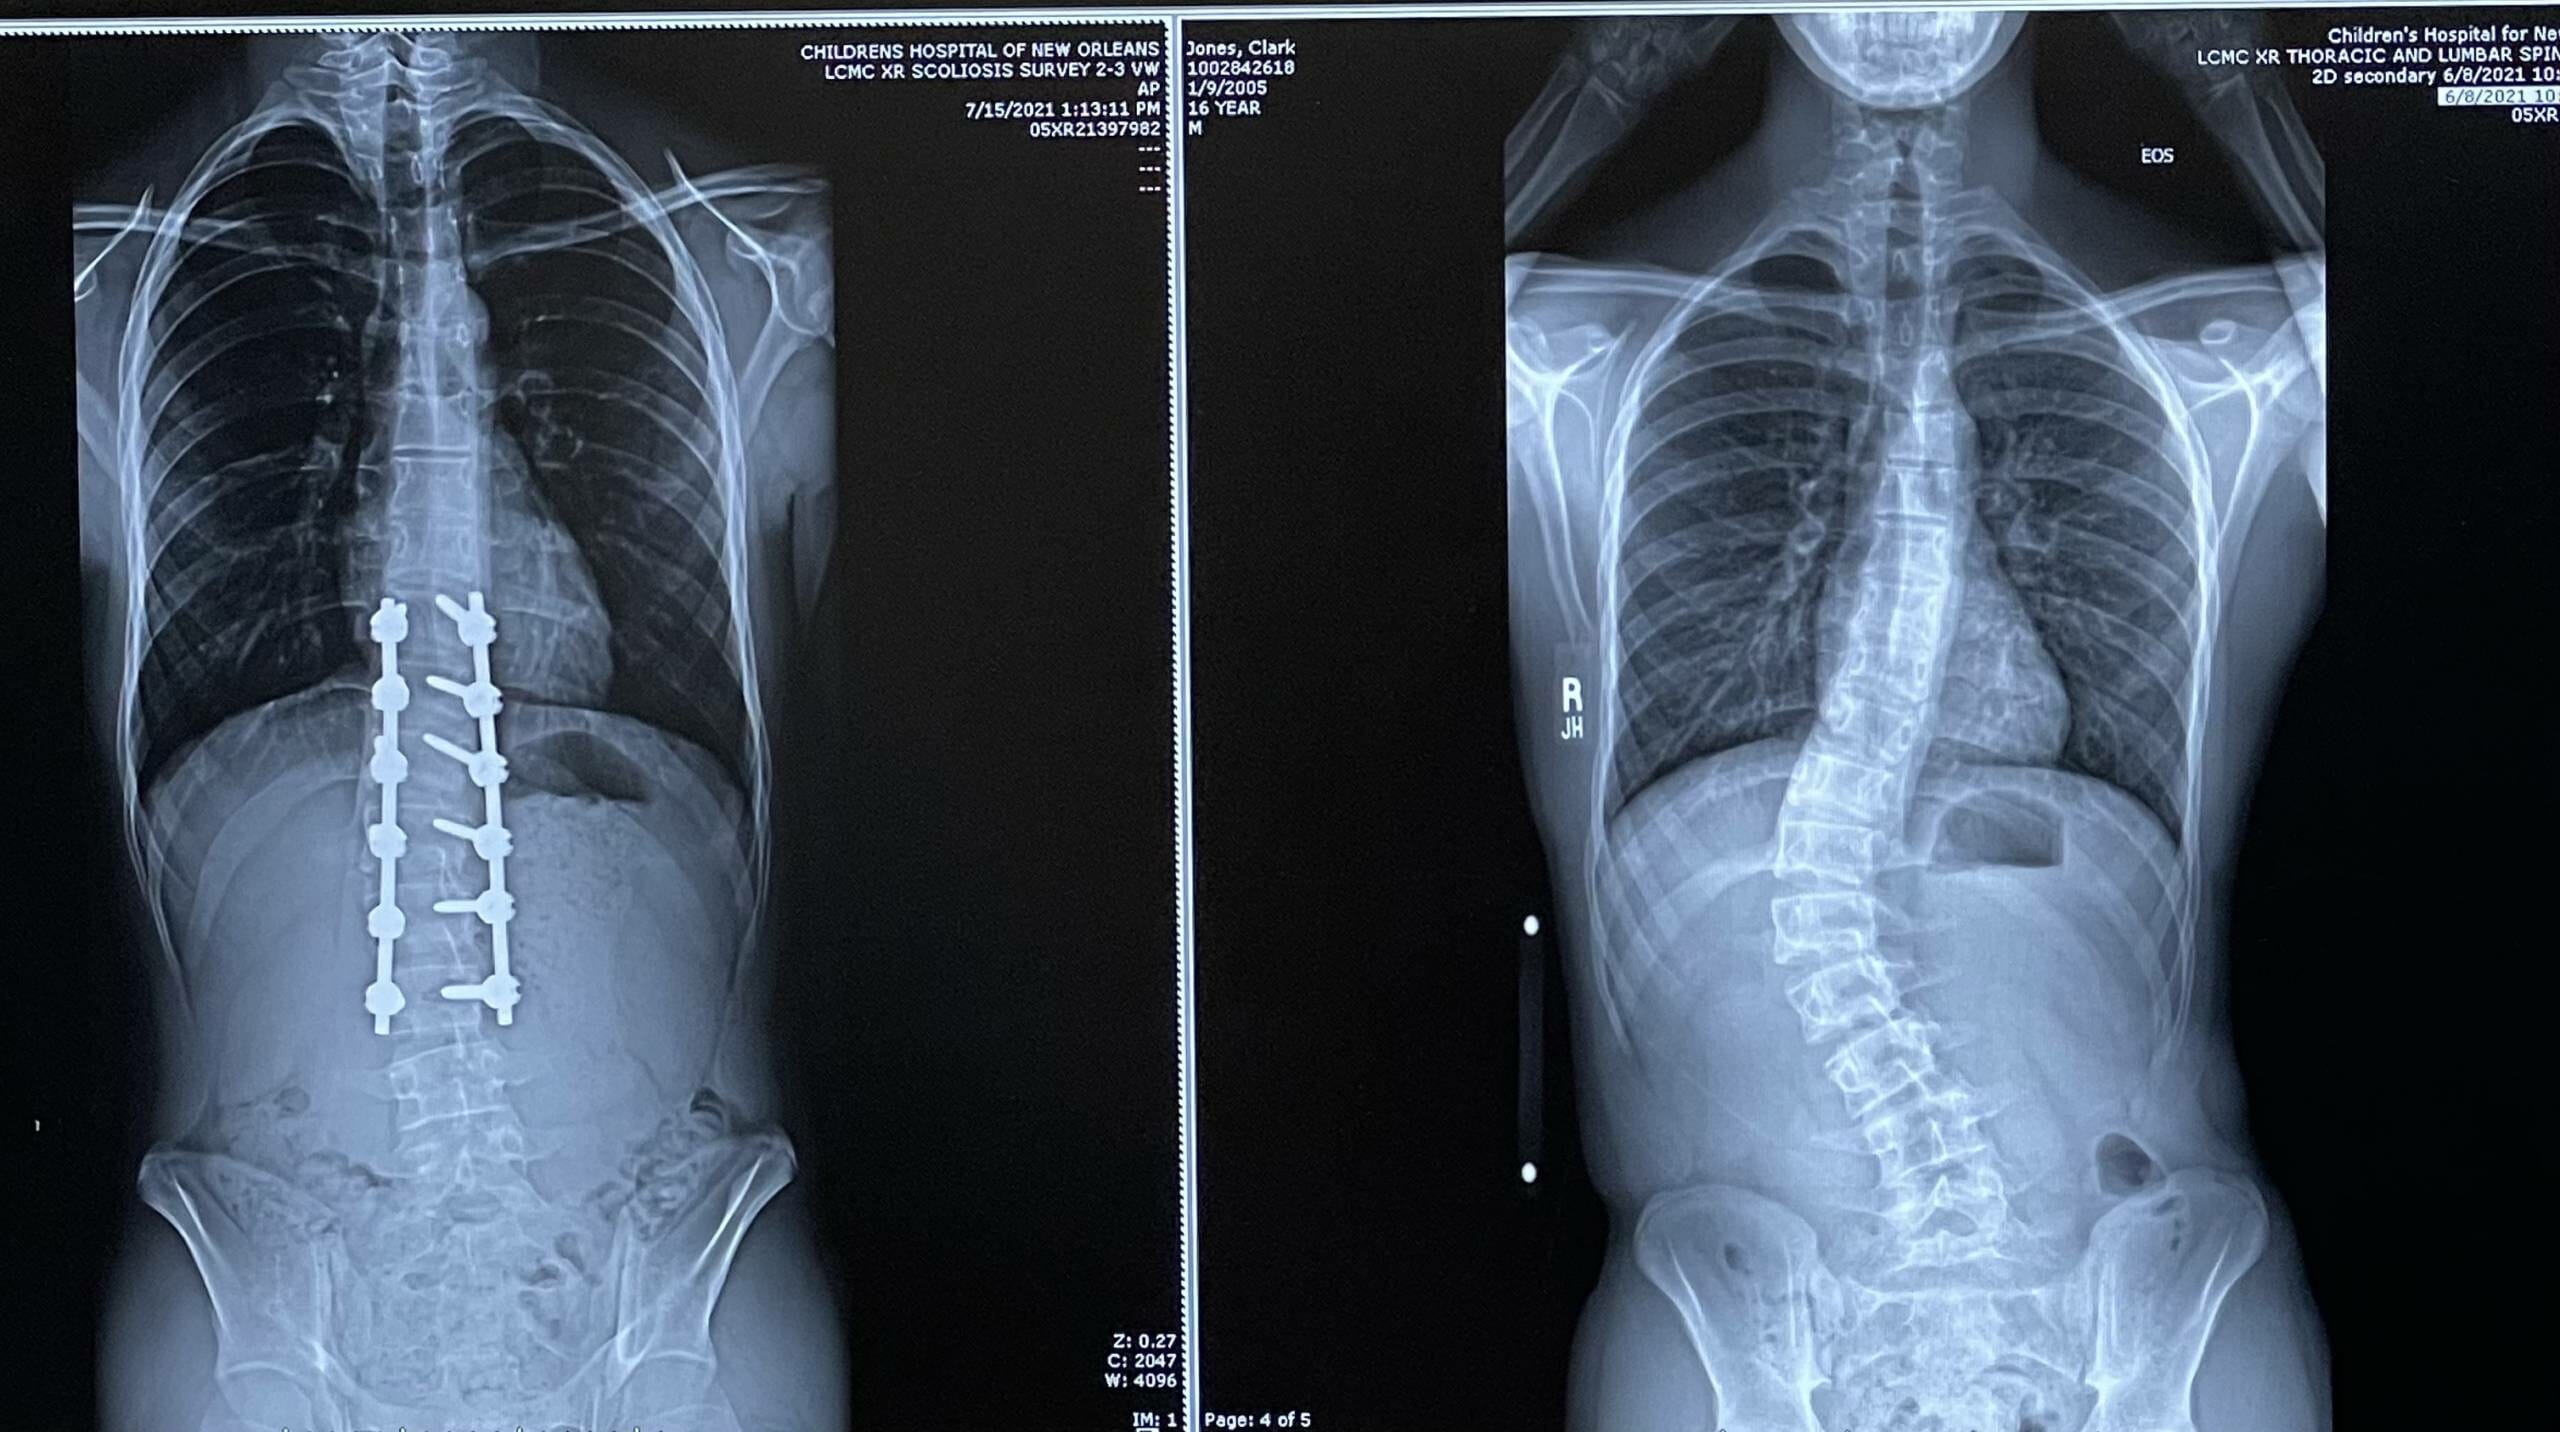

For Clark’s surgery, they shaved off some of his vertebrae to accommodate two titanium rods. The bone powder was used for a bone graft. The rods were aligned to the curve in his spine and they straightened his spine as much as was safe. Then the rods were screwed to his vertebrae and the vertebrae were grafted together so eventually, they will all be fused. That means that he will lose any mobility and remaining growth in that portion of his spine. His surgeon could have straightened his spine even more if he had fused down one more vertebrae, but he felt that having that mobility in the lowest part of his spine/hips was more important than getting a little more straightness (and we agree.)

We’re about 5 1/2 weeks post-op and he hasn’t taken any Tylenol, Advil, or Valium for probably a week or more. He was on oxycodone for probably 10 days post op, tapering down as needed. He had his first post-op appointment with his surgeon a couple of weeks ago and he was VERY pleased with Clark’s recovery–scar looks good, x-rays look good, Clark himself looked good.

He is cleared to drive and he’s been going to rehearsals for his high school’s production of Hairspray (he’s Corny Collins). He can feel the rods, but they don’t really bother him other than the fact that they’re in his back and never coming out. He isn’t in any pain (other than occasionally the incision) and is actually in less pain now than he was before the surgery. He’s able to sit for sometimes hours at rehearsal and is fine, whereas before the surgery, that would knock him out.

Q: Does he have rods?

A: Yes, he has two rods screwed into the vertebrae that were corrected.

A: Yes, by about an inch.